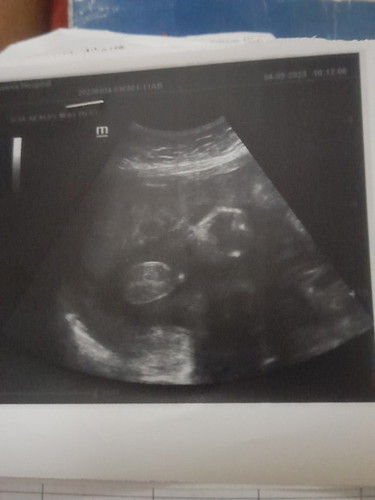

ช่วยดูให้หน่อยคะแม่ๆๆว่าเป็นผู้หญิงหรือผู้ชายซาวตอน24วีคเป็นหญิงพอ34วีคหมอบอกว่าชายเราไม่รู้เชื่อไหน